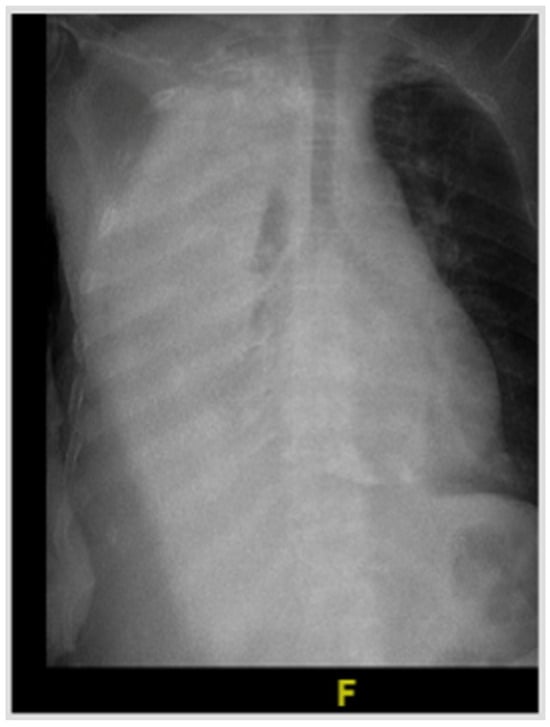

Beyond the Ordinary: Diagnosing a Case with Urinothorax

Tarneem M. Alghamdi, Mohammed M. Mergani, Habib Abdulnabi, Abdulaziz K. AlNaimi, Mohammed D. Al Shubbar, Hisham Y. Alouhali and Mahmoud I. Mahmoud

J. Respir. 2026, 6(1), 3; https://doi.org/10.3390/jor6010003 - 3 Feb 2026

Urinothorax, the presence of urine in the pleural space, is an exceptionally rare cause of pleural effusion, with fewer than 100 cases described in the literature. It most often follows trauma or urological procedures, though obstructive uropathy is also a recognized mechanism. We

Urinothorax, the presence of urine in the pleural space, is an exceptionally rare cause of pleural effusion, with fewer than 100 cases described in the literature. It most often follows trauma or urological procedures, though obstructive uropathy is also a recognized mechanism. We report an 83-year-old man with chronic kidney disease and benign prostatic hyperplasia who presented with acute dyspnea and a massive right-sided pleural effusion. Thoracentesis yielded clear yellow fluid with an ammonia-like odor, while imaging revealed chronic bladder outlet obstruction with bilateral hydroureteronephrosis. Despite inconclusive scintigraphy, the effusion resolved completely after urinary decompression with Foley catheterization, confirming the diagnosis. This case underscores the diagnostic challenges of urinothorax, which may be overlooked due to its rarity and variable biochemical profile, and highlights the importance of correlating clinical, radiologic, and pleural fluid findings. Early recognition is crucial, as timely relief of urinary obstruction provides both definitive diagnosis and curative treatment.

Full article

Figure 1